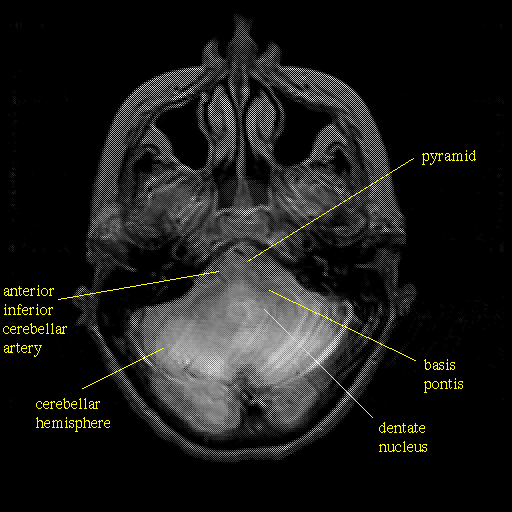

Pointers

Labeled